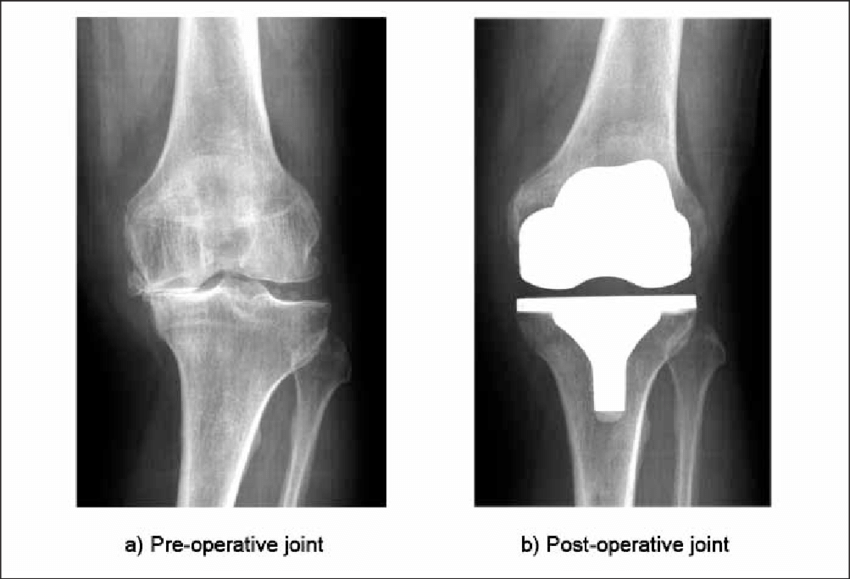

Knee replacement surgery, also known as Total Knee Arthroplasty, involves replacing the damaged cartilage and bone surfaces of the knee joint with smooth, durable artificial components.

Modern knee implants are designed to closely mimic natural knee movement and are highly durable.

Longevity of the ImplantWith appropriate care and activity modification, modern knee implants typically last 15–25 years.